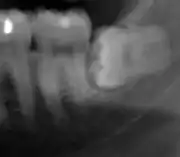

Coronectomy

Coronectomy is a procedure where the crown of the impacted wisdom tooth is removed, but the roots are intentionally left in place. It is indicated when there is no disease of the dental pulp or infection around the crown of the tooth, and there is a high risk of inferior alveolar nerve injury.[31]

Coronectomy, while lessening the immediate risk to the inferior alveolar nerve function has its own complication rates and can result in repeated surgeries. Between 2.3% and 38.3% of roots loosen during the procedure and need to be removed and up to 4.9% of cases require reoperation due to persistent pain, root exposure or persistent infection. The roots have also been reported to migrate in 13.2% to 85.9% of cases.[31]